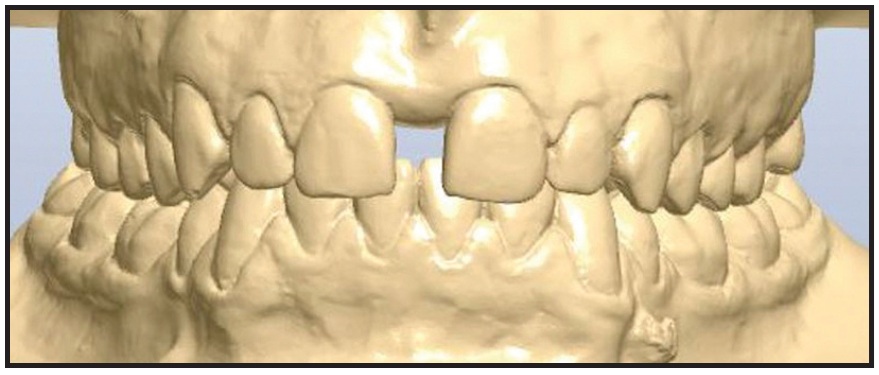

Four miniscrews (2mm in diameter) were inserted in the palatal vault: two 15mm miniscrews in the front, one 13mm miniscrew in the posterior right side, and one 15mm miniscrew in the posterior left side (Fig. 13). A TSE was placed, and the patient was instructed to perform two activations per day. The palatal expansion was completed after 21 days, when a diastema had developed between the central incisors as a result of opening the midpalatal suture (Fig. 14).

Fig. 13 Case 2. TSE anchored by four miniscrews.

Fig. 14 Case 2. After 21 days of expansion.

At this point, the bilateral crossbite was still present. A new impression of the upper arch was used to simulate surgical forward movement of the maxilla into a Class I canine relationship (Fig. 15). Because this diagnostic simulation showed that the transverse expansion was adequate (Fig. 16), we decided to block the TSE and proceed with surgical-orthodontic treatment. The amount of expansion ranged from 6.1mm in the anterior region to 5.71mm in the posterior region (Fig. 17). No dental or periodontal side effects were observed, nor was any buccal tipping or molar protraction (Fig. 18).

Fig. 15 Case 2. Diagnostic simulation of maxillary advancement.

Fig. 16 Case 2. A. Before treatment. B. After expansion.

Fig. 17 Case 2. Expansion of midpalatal suture.

Fig. 18 Case 2. A. Before treatment. B. After expansion. C. Superimposition of pre- and post-expansion models.

Treatment was completed in a total of 20 months using a combination of fixed labial appliances and orthognathic surgery.